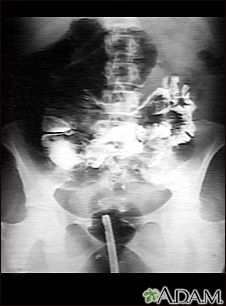

Volvulus - x-rayBackVolvulus - x-rayA GI series in a patient with a twisted bowel (volvulus). E-mail FormEmail ResultsName:Email address:Recipients Name:Recipients address:Message: